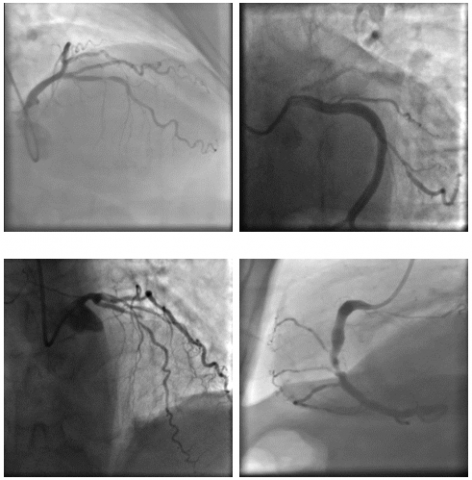

The image dataset utilized in this study was sourced from a publicly available repository provided by Danilov et al. [9]. The images, similar to those given in Figure 2, were captured using high-end imaging systems, namely the Coroscope (Siemens) and Innova (GE Healthcare), which are widely used in clinical practice for precise visualization of coronary arteries.

The dataset comprised angiographic scans from 100 patients, each of whom had been clinically diagnosed with single-vessel coronary artery disease, either through functional assessments or direct angiographic evaluation. The dataset featured a total of 8,325 grayscale images, with resolutions ranging from 512×512 to 1000×1000 pixels, ensuring detailed visualization of the vascular structures. These high-quality images provided an excellent basis for training and evaluating deep learning models, particularly for detecting stenotic regions. Details of each step employed for detecting CAS from XCA images are provided below and are depicted in Figure 3.

Figure 2. Sample angiography images included in the data set [9]